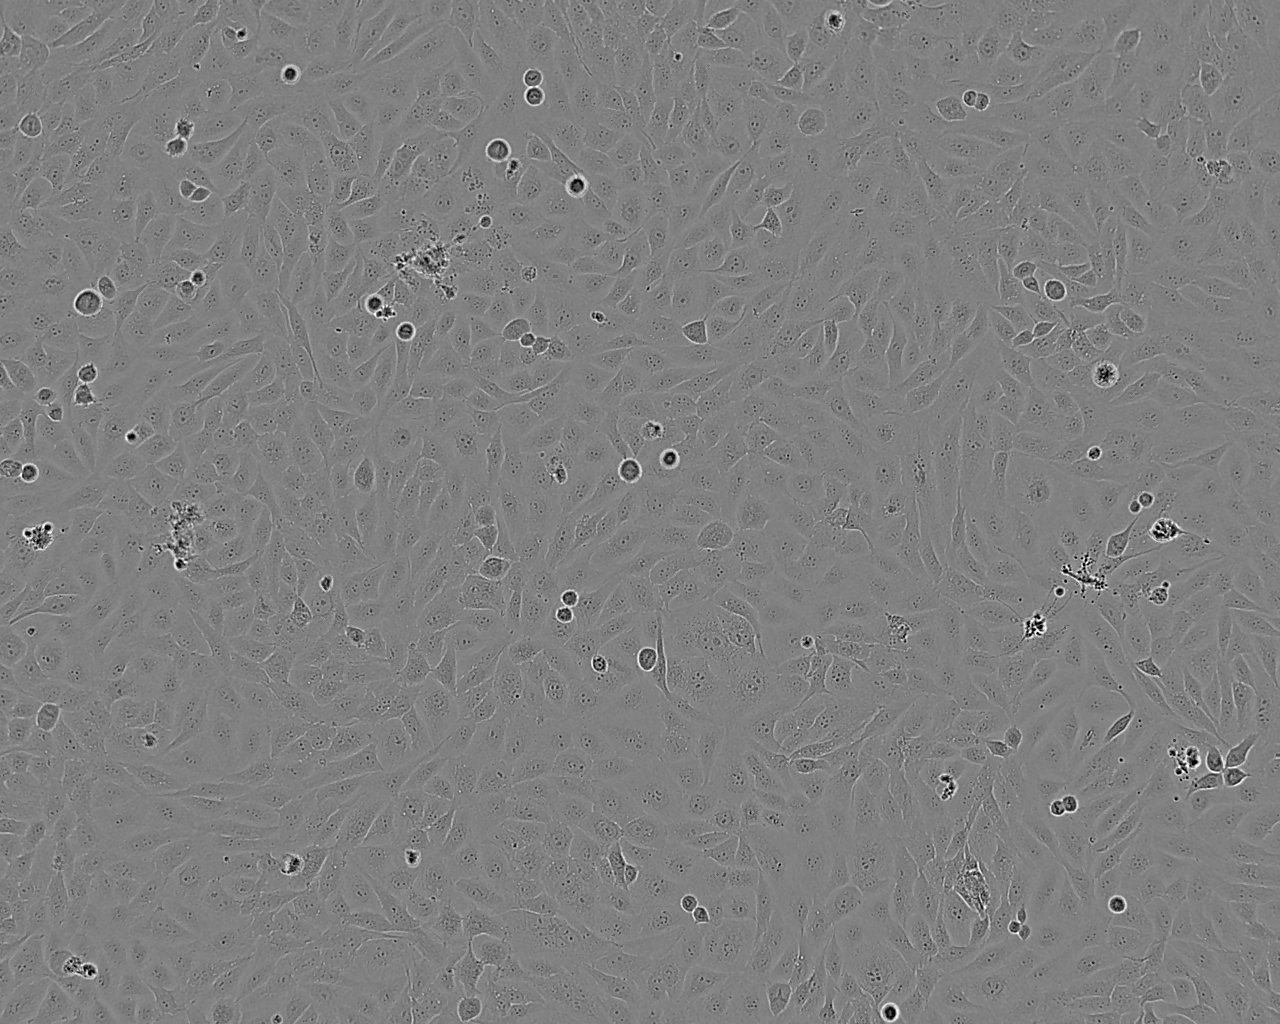

COR-L26 人肺癌细胞系

细胞形态:上皮细胞样

细胞生长:贴壁

细胞传代方法:1:2-1:3传代;每周换液2-3次。